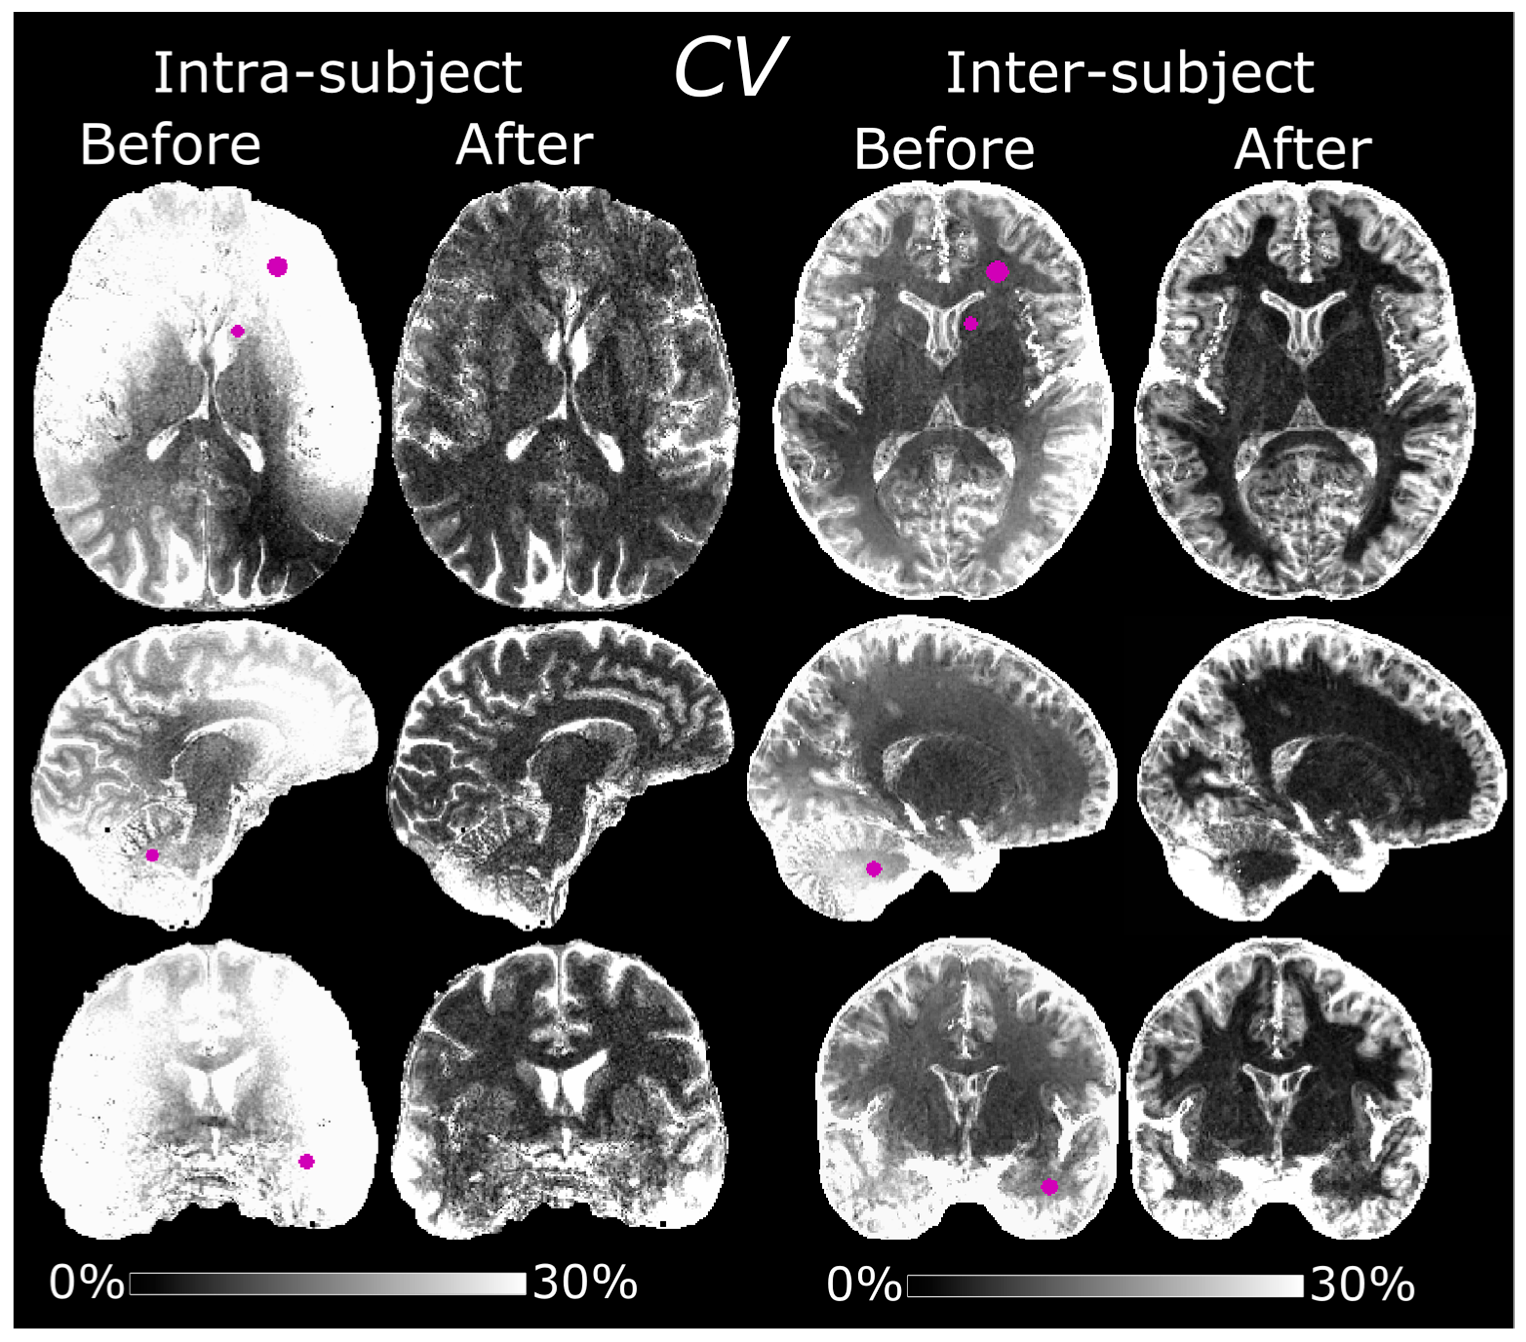

3.4. Intra-Subject Variability

The MPRAGE volumes, before and after normalization, are shown in Figure 4. The normalized volumes show a noticeably increased spatial homogeneity. Hyperintense pixel values in the temporal lobes and cerebellum of the normalized volumes are indicative of a failed inversion with the adiabatic pulse [24]. These bright pixel intensities were exacerbated in session #4, possibly due to a transmitter adjustment failure. Before normalization, the average CVs were 20 ± 7.8% in WM, 32 ± 12% in GM and 46 ± 19% in CSF (Figure 5). The corresponding values after normalization were 7.9 ± 3.3% in WM, 15 ± 7.0% in GM and 33 ± 16% in CSF. Exclusion of session #4 yielded an average CV of 16 ± 8.1/27 ± 14/39 ± 24% in WM/GM/CSF before normalization and 7.2 ± 2.5/11 ± 6.8/22 ± 14% after. The results of the ROI-based analysis can be seen in Table 2.

3.5. Inter-Subject Variability

The CV was substantially reduced after normalization also in the inter-subject comparison (Figure 5). This improved reproducibility was most evident in the WM and basal ganglia since the diffeomorphic registration made a pixelwise comparison difficult in the cortex. Before normalization, the average CVs in MNI space were 13 ± 7.8/22 ± 9.5/45 ± 20% in WM/GM/CSF, respectively. The corresponding values after normalization were 7.6 ± 7.6/18 ± 10/43 ± 24%. Based on individual segmentations, the CVs were 6.2/6.5/9.0% before normalization and 2.0/4.3/6.4% after in WM/GM/CSF. Results of the ROI-based analysis can be seen in Table 2.

Figure 4. MPRAGE volumes before (SMP) and after (SMP/GRE) normalization, acquired on a subject scanned at five separate sessions (day 1, 161, 170, 189, and 253). Influence from the bias field is noticeably reduced after normalization. Hyperintense pixels indicate a failed adiabatic inversion. At the 4th scanning session, there was possibly a transmitter adjustment failure, resulting in generally lower B1+ and thus a generally darker SMP image as well as a larger area of very bright pixels in the cerebellumum of SMP/GRE.

Figure 5. Maps of the CV before and after normalization, showing the intra- and inter-subject variability. The intra-subject CV maps were calculated from data acquired at five scanning sessions under an eight-month period. The inter-subject CV maps, in MNI space, were calculated from data acquired from 10 separate subjects. Reproducibility was improved after normalization in both cases. The ROIs corresponding to the data in Table 2 are denoted in purple in the “Before” maps.